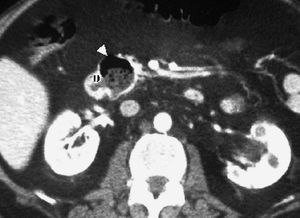

El duodeno es una localización infrecuente de diverticulitis. La imagen radiológica consiste en un engrosamiento de la pared del duodeno asociado a un divertículo, en ocasiones con un enterolito en su interior, con inflamación de la grasa adyacente16 (fig. 9).

Fig. 9--Diverticulitis duodenal. (A) En la ecografía se observa un divertículo (flechas) con engrosamiento de pared duodenal (D) y alteración de la grasa adyacente (*). (B) Tomografía computarizada de otro paciente con inflamación de divertículo duodenal. Se oberva una lesión quística (punta de flecha) de pared gruesa y borrosa, con material en su interior. P: Páncreas.